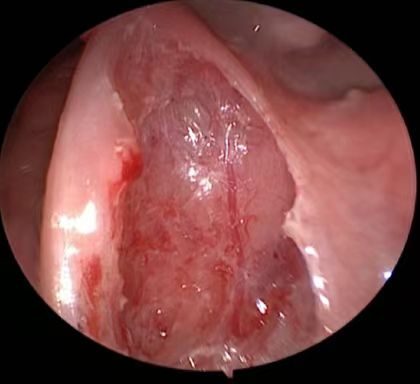

术后1周,周建波主任查看萱萱伤口

改良等离子扁桃体被膜血管保护技术

捷克论坛 耳鼻咽喉头颈外科三病区周建波主任医师介绍,儿童阻塞性睡眠呼吸暂停低通气综合征多由于扁桃体、腺样体肥大所致,多指睡眠状态下频繁出现呼吸暂停、睡眠中断、低通气等所致的一系列病理生理变化,需手术治疗。目前,捷克论坛 耳鼻咽喉头颈外科三病区不仅低温等离子射频消融术非常成熟,近年来通过不断探索,创新性地提出在等离子扁桃体手术中被膜血管保护技术,可以大大降低患儿手术创伤和术后痛苦,术后正常进食时间也大大缩短,术后康复过程明细加速,术后出血的概率远低于常规等离子手术,深受广大患儿及家长的欢迎。

周建波教授指出,常规等离子切除创面,其伪膜厚、疼痛明显,相对于成人,儿童疼痛耐受性差,有些患儿手术后切口疼痛拒绝进食,不愿吞咽、漱口,口腔卫生保持差,导致出现感染,从而使切口延迟愈合甚至出血等并发症的发生。而低温等离子消融术结合扁桃体被膜血管保护技术,其创面伪膜淡、疼痛轻微,明显加速了术后康复过程。(耳鼻咽喉头颈外科三病区   肖莉)